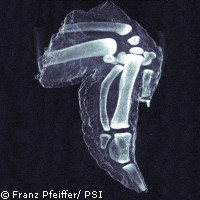

Alcuni ricercatori europei hanno sviluppato un modo per produrre immagini a raggi X estremamente dettagliate mediante l'impiego di apparecchiature di imaging convenzionali, quali quelle utilizzate negli ospedali e negli aeroporti. La nuova tecnica produce immagini cosiddette «a campo oscuro», che potrebbero rivelarsi utili per numerose applicazioni, tra cui l'imaging medico e lo screening per la sicurezza. A differenza dei raggi X convenzionali, le immagini a campo oscuro catturano la diffusione dei raggi X all'interno del materiale stesso, mostrando le variazioni anche minime di ossa, tessuti molli e altri materiali. L'immagine prodotta è molto più chiara e dettagliata di quella ottenuta con i normali raggi X. In campo medico, la sensibilità potenziata del sistema si traduce nella possibilità di rilevare le microfratture e di misurare la densità ossea. Inoltre, poiché le cellule cancerose e delle placche diffondono le radiazioni in maniera diversa dalle cellule normali, le immagini a raggi X a campo oscuro dei tessuti molli potrebbero evidenziare i tessuti cancerosi e le placche associate al morbo di Alzheimer. La maggiore sensibilità dei raggi X a campo oscuro emerge chiaramente nell'immagine di un'ala di pollo pubblicata insieme all'articolo nella rivista «Nature Materials». Nel contesto di sicurezza, la struttura microcristallina degli esplosivi fa sì che diffondano le radiazioni in maniera marcata e siano pertanto facili da individuare con i raggi X a campo oscuro. Nell'industria marittima e aeronautica, tali raggi X potrebbero essere utilizzati per individuare microcrepe e corrosione in strutture quali gli scafi delle navi e le ali degli aeroplani. Tuttavia, il pieno potenziale di tali raggi X a campo oscuro non è stato finora praticamente mai sfruttato, in quanto la loro produzione era possibile solamente mediante l'impiego dell'ottica cristallina, estremamente complessa, e delle fonti di raggi X più luminose del mondo, quali i sincrotroni. Nel loro articolo, gli scienziati danesi e svizzeri spiegano l'utilizzo di reticoli nanostrutturati montati su fonti convenzionali di raggi X al fine di produrre immagini a campo oscuro. «I ricercatori lavorano da anni sulle immagini a raggi X a campo oscuro», ha commentato il professor Franz Pfeiffer del Paul Scherrer Institute e École polytechnique fédérale de Lausanne (Svizzera). «Fino a oggi tali immagini sono state prodotte solamente utilizzando elementi ottici cristallini sofisticati», ha aggiunto Christian David del PSI. «La nostra nuova tecnica utilizza componenti ottici innovativi dei raggi X sotto forma di reticoli di nanostrutture che consentono l'impiego di uno spettro energetico ampio, compresa la gamma standard di energie utilizzata nelle apparecchiature convenzionali per i raggi X in uso negli ospedali o negli aeroporti.» Gli scienziati hanno ora intenzione di adattare il sistema per renderlo utilizzabile con le apparecchiature medicali esistenti. «Se combiniamo questa tecnica con quella di imaging a contrasto di fase sviluppata nel 2006, abbiamo la possibilità di fornire la stessa gamma di tecniche di imaging nell'imaging a raggi X ad ampio spettro che possiamo offrire per la luce visibile», ha affermato il professor Pfeiffer.